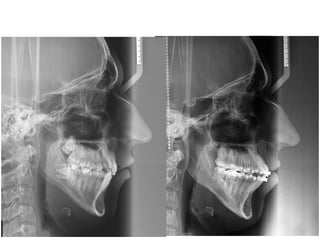

Superposição da Mx sobre PP c/ registro em ENA

Finalidade: avaliar as

movimentações dentárias

Ocorreu movimento distal de

molares e projeção de dentes

anteriores.

Superposição da Md sobre Borda inf. Md c/

registro na Cortical interna da Sínfise

movimentações dentárias Ocorreu movimento distal de

ANB 4° Wits 2mm FMA29° GoGn.SN 36° Is-NA 9° Is.NA 1mm Ii-NB 23° Ii.NB 4mm IMPA 88° Elementos de Diagnóstico Perfil Mole Facial Convexo | Padrão Vertical | Nariz Proeminente Assimetria Discreta | Linha do Sorriso Adequada Classe I | Overbite | Mordida Cruzada Post-direita | Mordida Aberta 12/43 DM = - 10,2 mm Spee = -3 mm DC = - 1,6 mm IMPA 88° 18a 3m